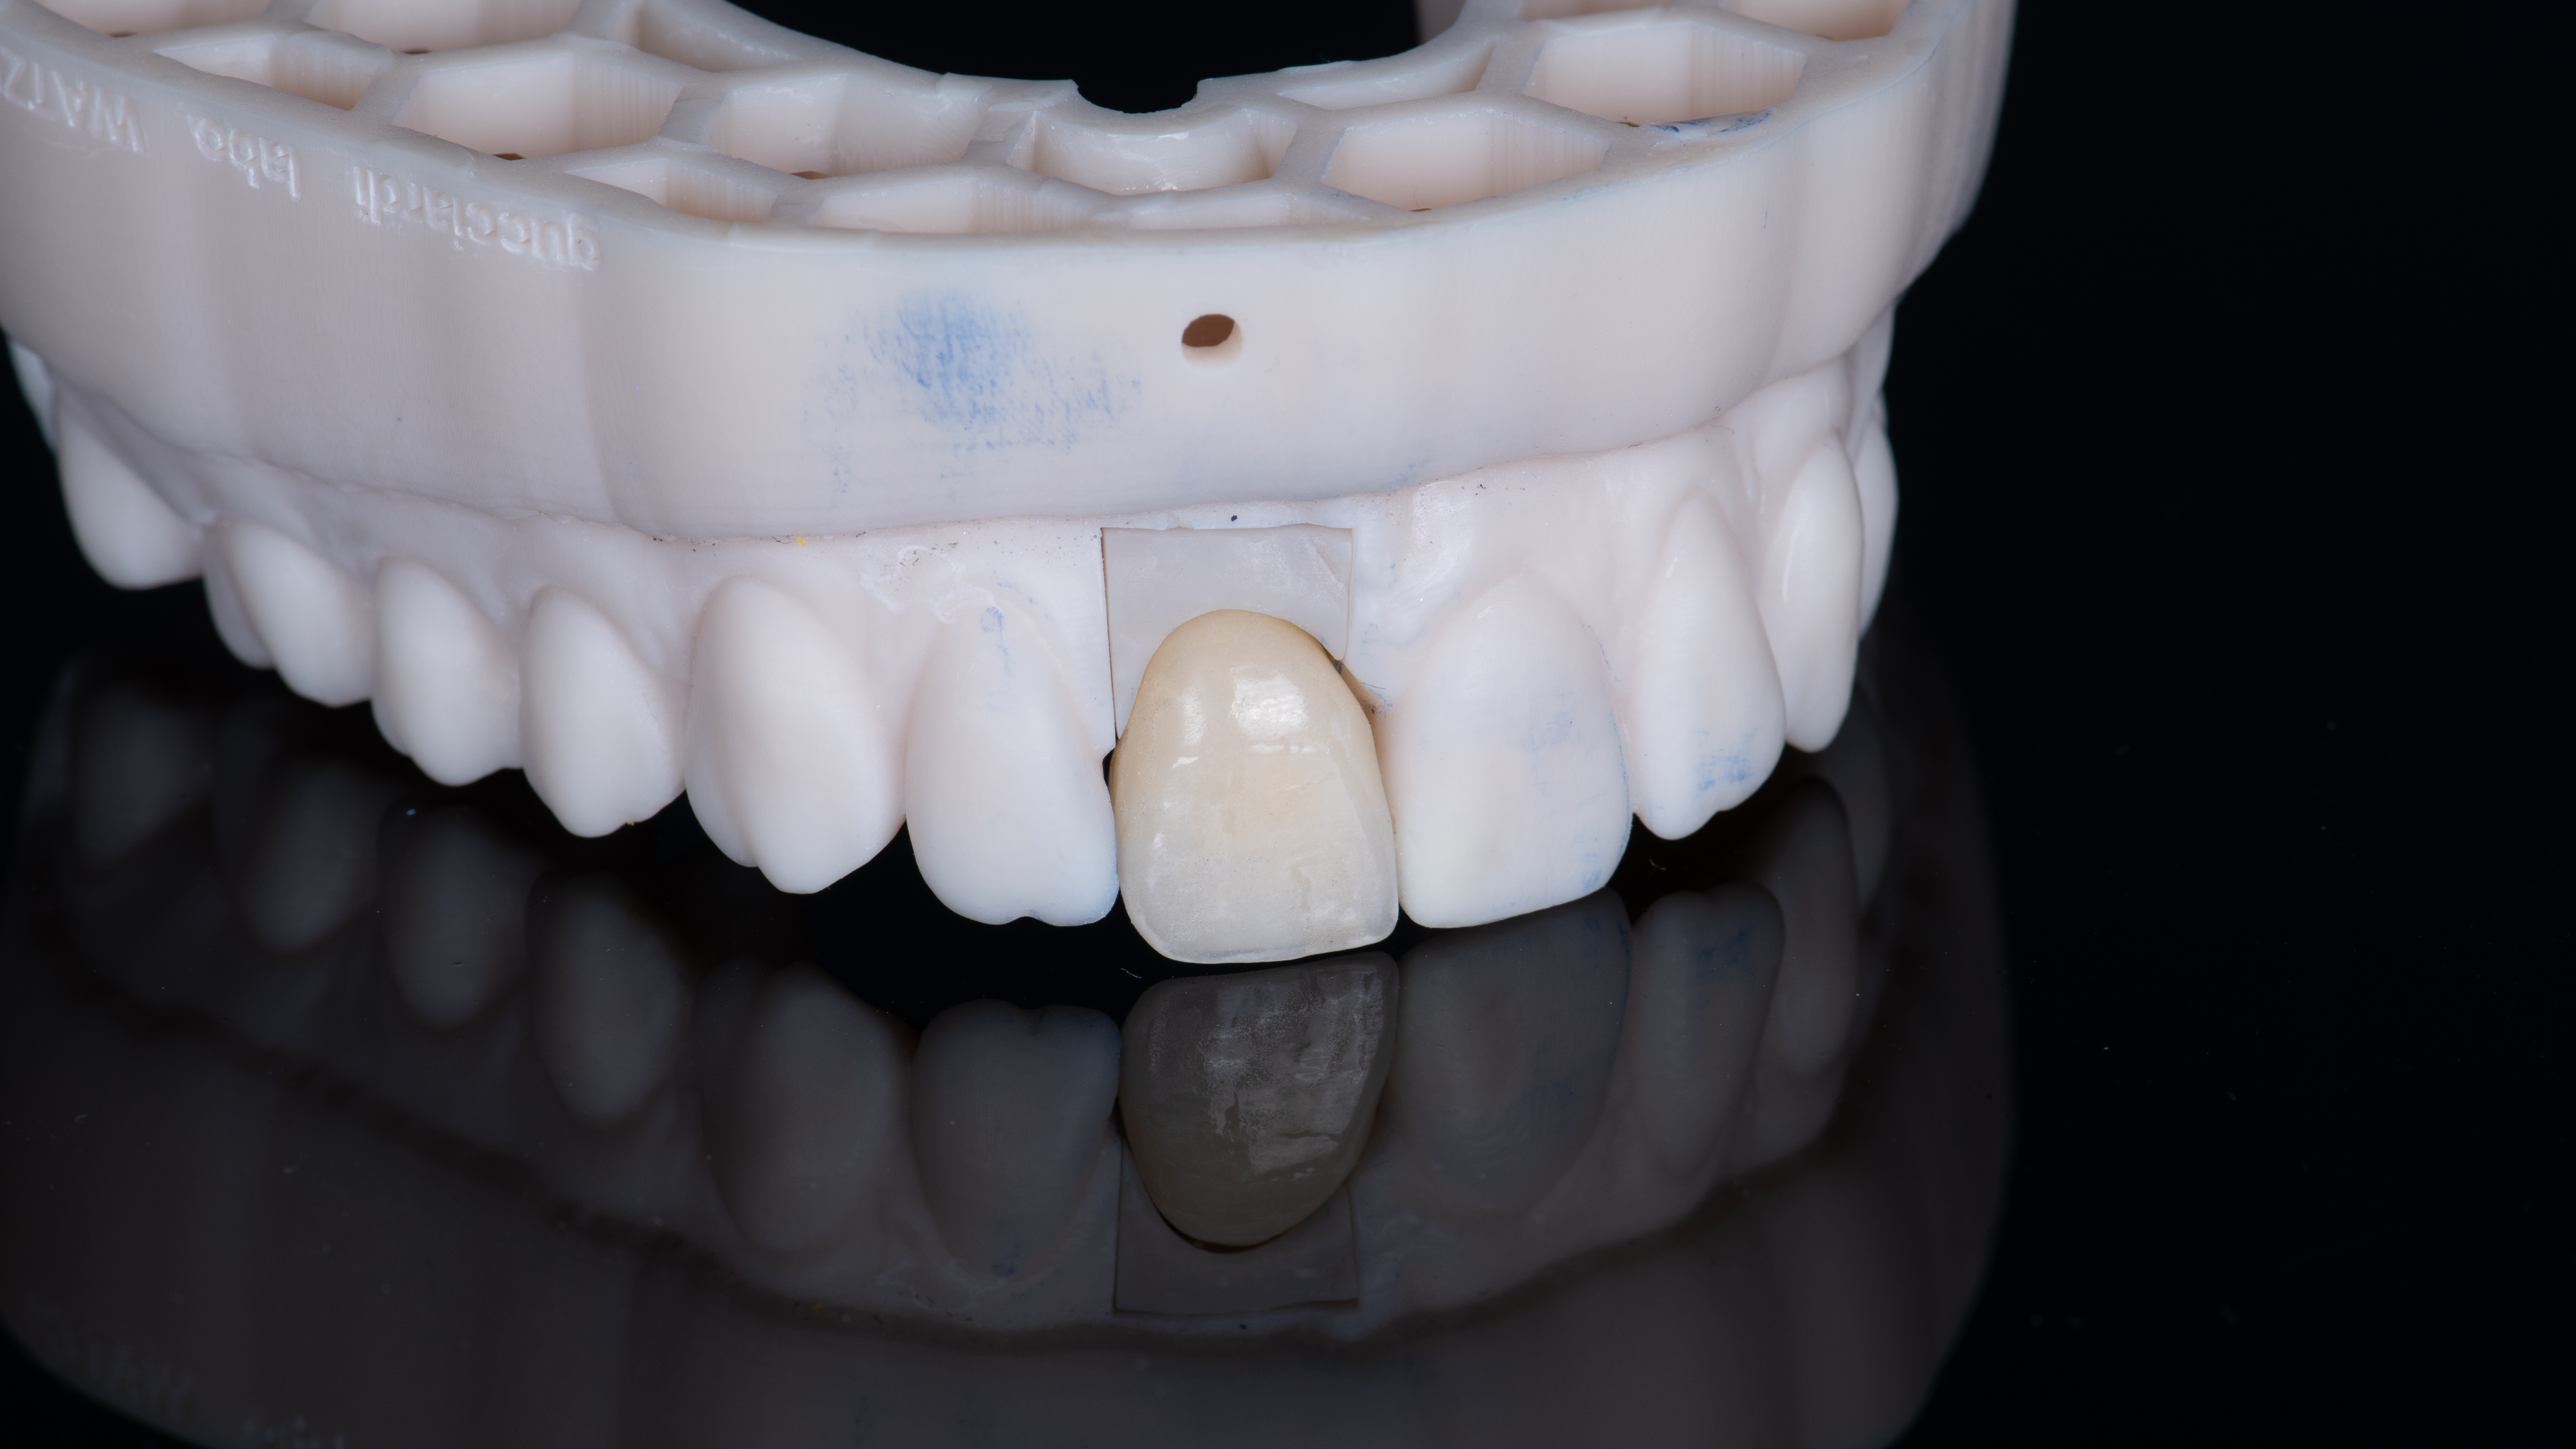

Une copie de la couronne de la patiente est imprimée et évidée pour permettre de la positionner correctement. Elle est ensuite solidarisée à un pilier provisoire vissé dans l’implant. Ceci nous permet ensuite d’ajuster le profil d’émergence (Photo 12).